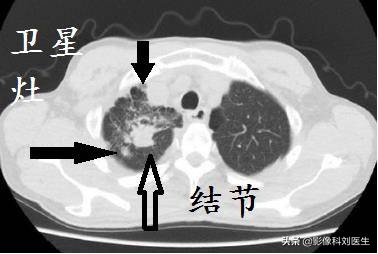

在胸片上有时表现为肿块样改变,而CT横断扫描每一层所表现出的病灶,往往是斑片状、棉絮状、索条状或空洞,每层形态各一,不能堆塑成肿块,这是因为X线片是重叠图像,而CT分层图像。既使是结核球,它也具有结核的特征,即多灶性表现为卫星灶、多钙化性表现为环状钙化或整个球形病变CT值高>80Hu,易与肺癌相鉴别。

直径>3 cm的肺结核由于形态较大,范围常累及多段,病变可出现在肺结核非好发部位,如上肺前叶、右肺中叶及下肺内、后基底段等。卫星灶是诊断肺结核的重要征象之一,约有37.1%的肺结核患者可见卫星灶。 卫星灶、密度不均、钙化、尖角样突起、洞壁光整等征象都支持肺结核诊断 。蜂窝状强化与包膜样强化是直径>3 cm肺结核的主要强化特征,尤其是蜂窝状强化在该类肺结核中较常见。